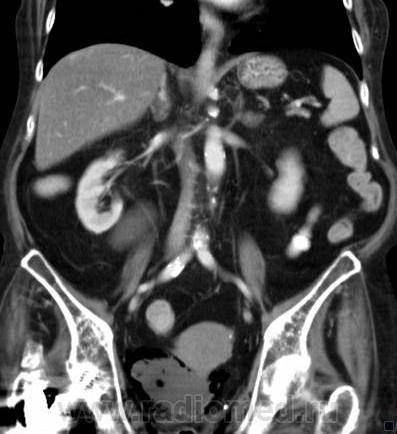

О чём могут говорить такие "газовые структуры" в области мочевого пузыря?

Наличие газа в мочевом пузыре может говорить о многом. Например стоял катетр Фолея, состояние после цистоскопии, эмфизематозный цистит, наличие фистулы.

А, чем именно, будет характеризоваться эмфизематозный цистит? При нем "пузырьки газа" локализуются в слизистой оболочке или где?

В просвете, может быть и в самой стенке. Смотрите здесь:

процесс в стенке в данном случае.

У женщины киста правой почки, подозрение на жировой гепатоз, стержень в головке и шейке правого бедра (остеосинтез). А про воздух возле/в стенке мочевого пузыря... не было ли оперативного вмешательства в малом тазу? И без аксиальных срезов явно я бы не сказала, где конкретно воздухblush...

Фик с ней с кистой... И какая разница аксиалы и короналы... Да, толстоваты срезы, эффект усреднения. Но я бы думал в сторону язвенного/гангренозного цистита (эмфизематозного цистита). Естественно, анамнез и клиника и всё встанет на свои места. На состояние после катерера не очень похоже...